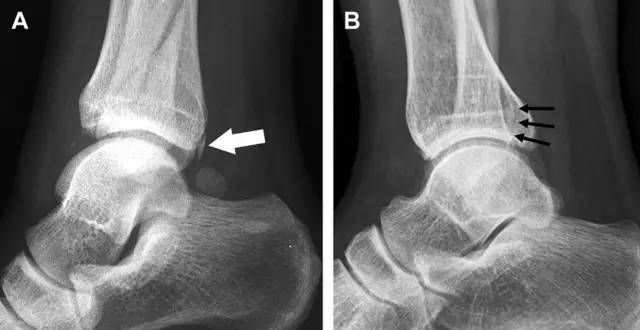

距骨外侧突骨折常因踝外翻背屈时,跟骨上外侧面撞击距骨外侧突下缘导致,或偶尔由踝内翻引起,被称为「滑雪板者骨折」。这种骨折只能在踝关节正位片上发现,而且外踝远端表面软组织肿胀往往是一个重要线索(图 4)。

图 4 距骨外侧突骨折。A 正位片示内翻损伤所致的距骨外侧突撕脱性骨折(箭头);B 另一位患者,踝外翻损伤导致典型的「滑雪板者骨折」,X 片上可见一较大的三角形骨折块(方框);C 第二位患者的 MRI 矢状位 T1 加权像示横行骨折(箭头)